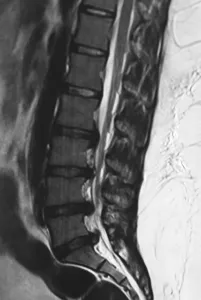

Multiple level disc prolapses in a 17 years old girl

Some of them have a variation in the anatomy of segments on the lower spine that puts one of the discs at risk of higher stresses and an accelerated wear and tear leading to a disc prolapse at a young age. Another reason is a genetic variations that can lead to accelerated disc degeneration at multiple levels in the entire spine. Multiple level lumbar disc prolapses at a young age are commonly found in such patients. A strong family history of similar problems is almost always there in such patients. Multiple level disc problems can lead to loss of normal curvature of the lumbar spine and result in a flat back or a bend to one side in some adolescents.